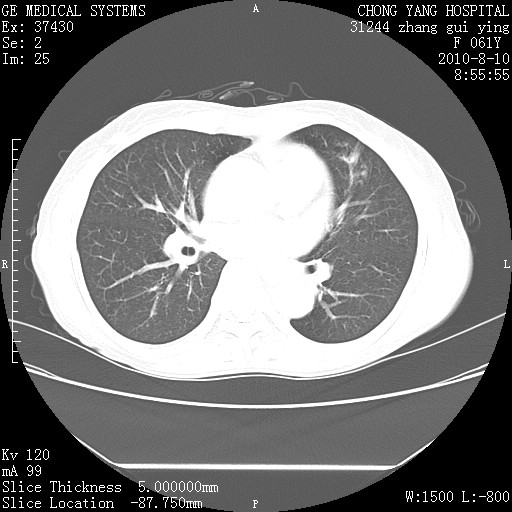

标题: CT28314:F61Y胸部增强,发热咳嗽一周入院,后面的为一周前平 [打印本页]

标题: CT28314:F61Y胸部增强,发热咳嗽一周入院,后面的为一周前平

1、支持考虑右侧中央型肺癌伴右肺中叶节段性不张及下叶支气管黏液痰栓    2、左肺上叶舌段感染。

确切的说:1:右肺下叶中心型肺癌侵及中叶支气管并中叶不张,纵膈淋巴结转移。2:左肺舌叶炎症。3:右侧胸腔少量积液

1:右肺下叶中心型肺癌侵及中叶支气管并中叶不张,纵膈淋巴结转移。2:左肺舌叶炎症。3:右侧胸腔少量积液。支持!

右肺下叶中心型肺癌侵及中叶支气管并中叶不张,纵膈淋巴结转移。2:左肺舌叶炎症。3:右侧胸腔少量积液